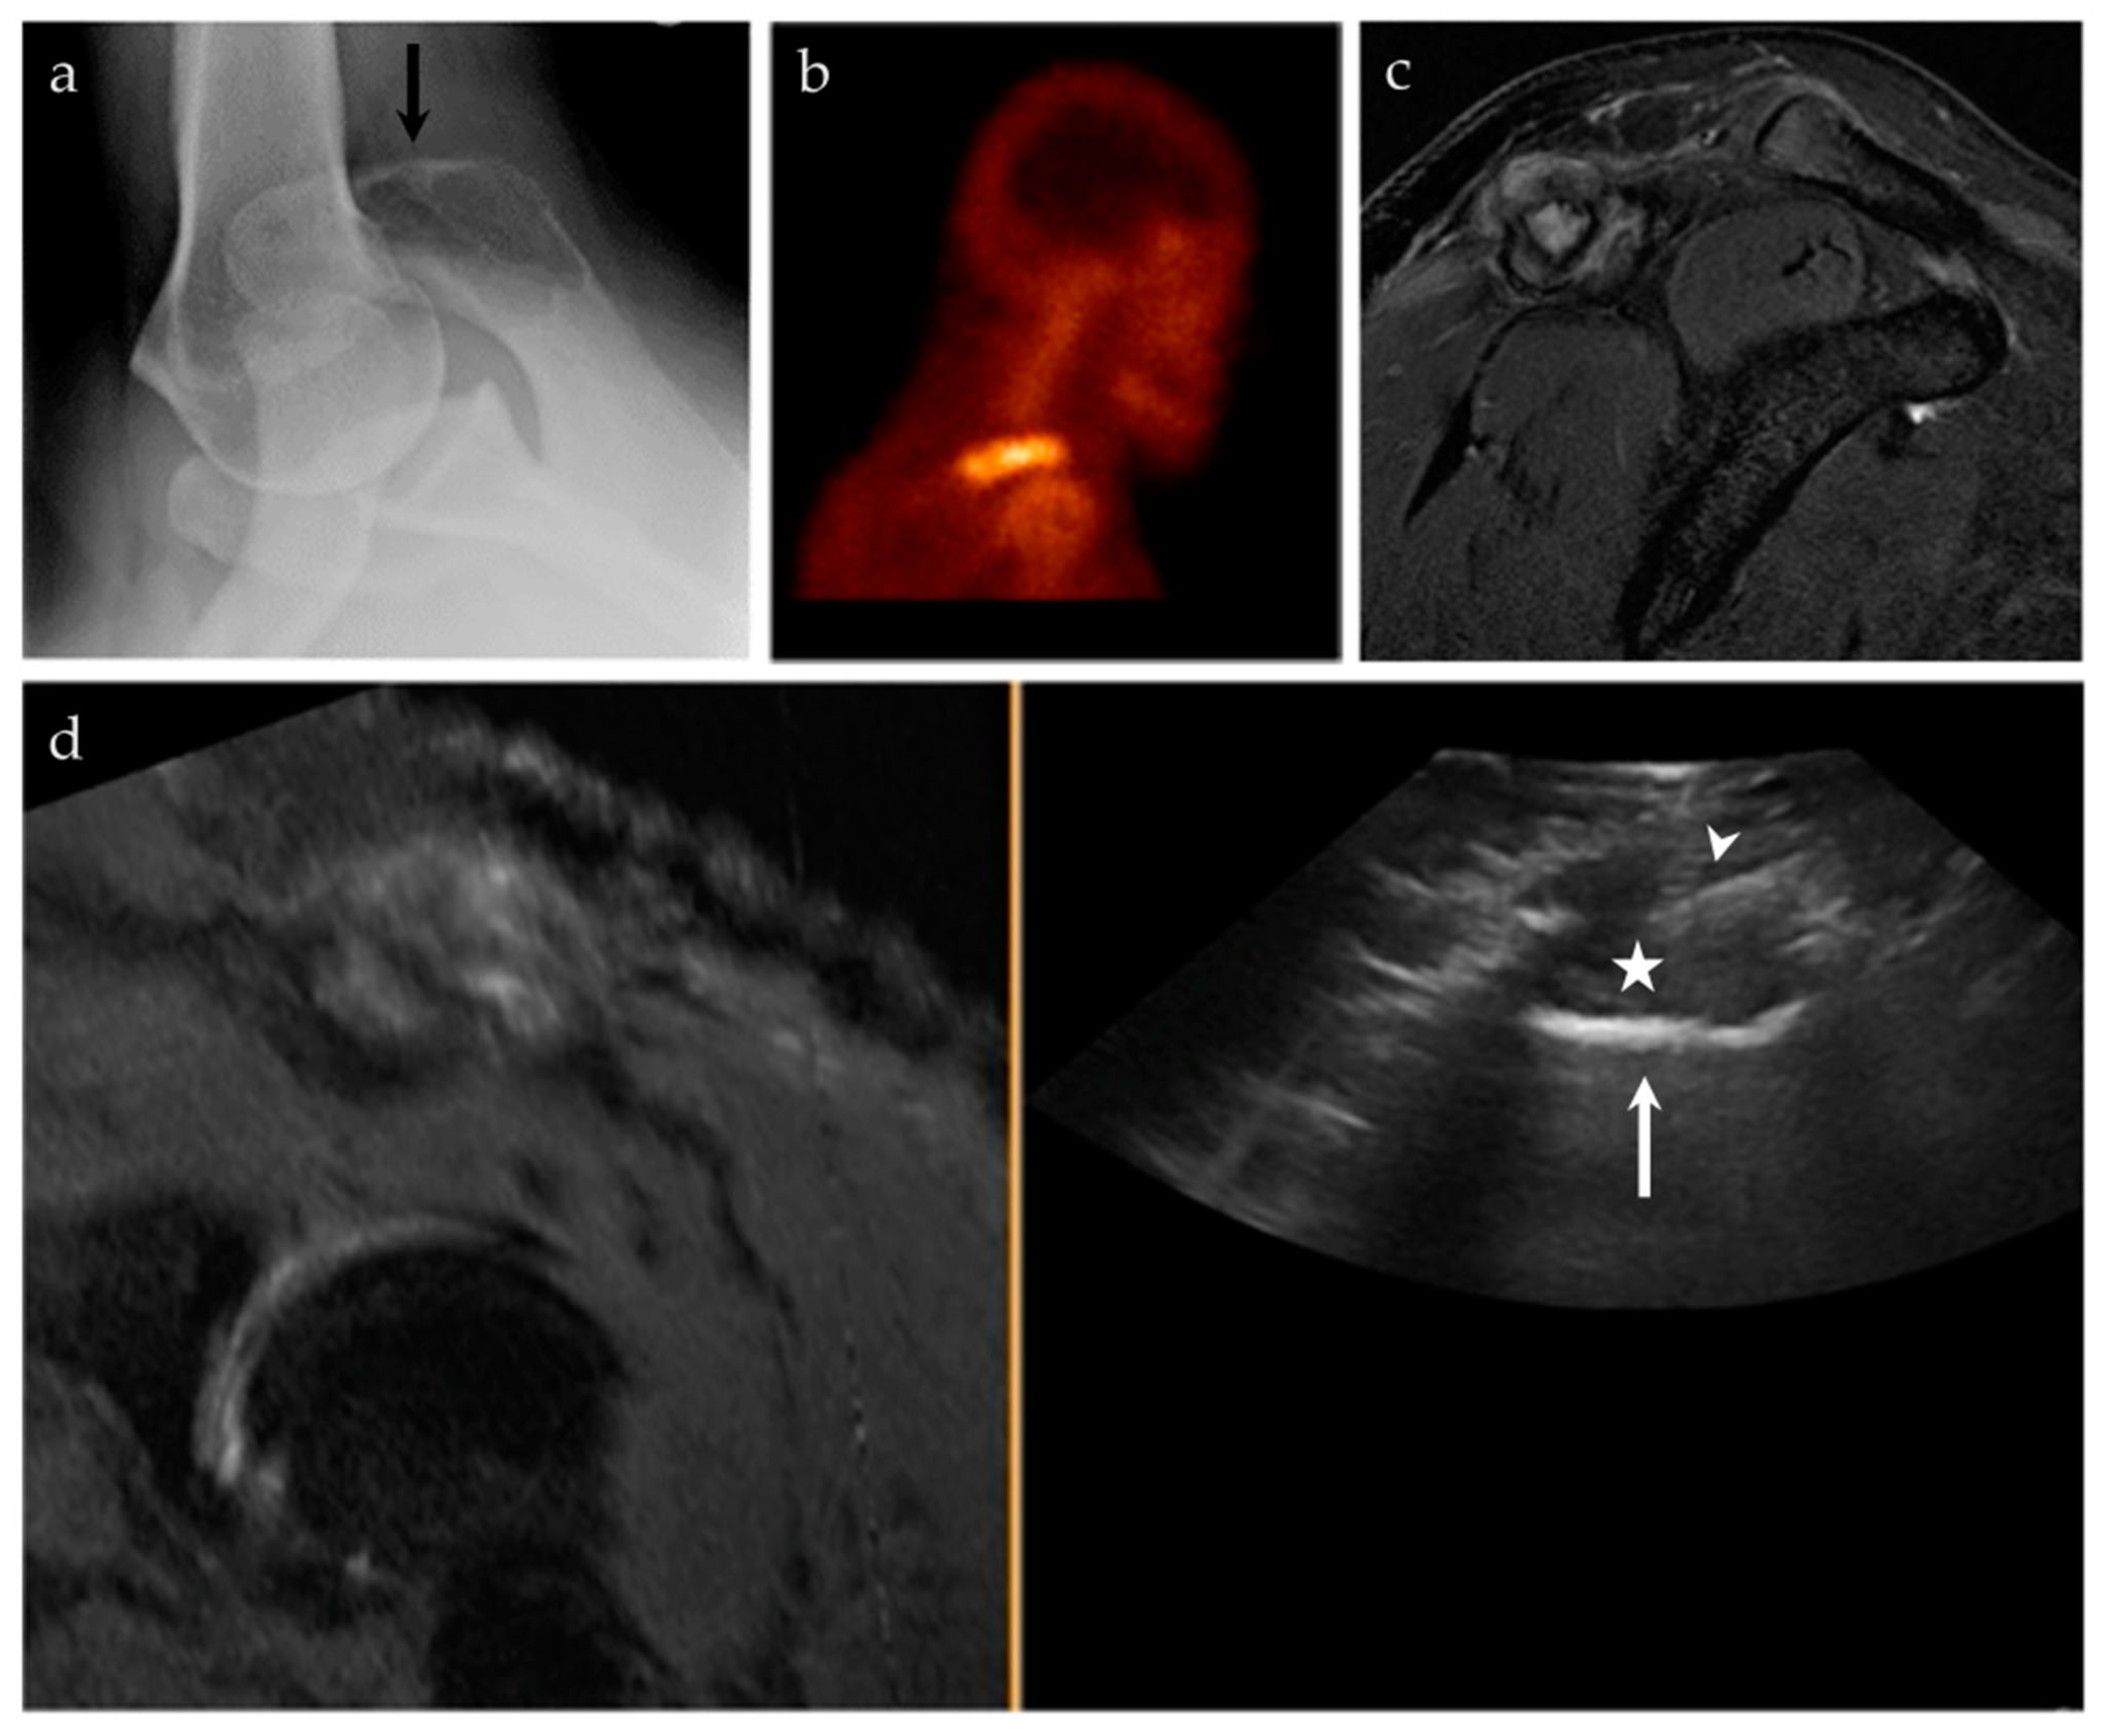

3.2.4. Targeted Percutaneous Lesion Biopsy and/or Aspiration

| 17/M | Acromioclavicular joint | US-MRI | Metastatic disease, nasopharyngeal carcinoma | Neoplastic, malignant |

| 54/F | Left midfoot | US-MRI | Metastatic disease, melanoma | Neoplastic, malignant |